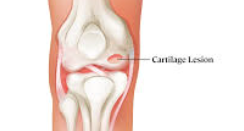

무릎 연골 손상 시 특징적으로 나타나는 증상 중 하나는 관절에서 나는 소리입니다. 무릎을 구부리거나 펼 때 '딱딱', '삐걱' 하는 소리가 나며, 이를 의학적으로 '관절음'이라고 합니다. 이는 손상된 연골 표면이 거칠어져서 뼈와 뼈 사이의 마찰이 증가하기 때문입니다.

손으로 무릎을 만지면서 관절을 움직여보면 뼈끼리 문지르는 듯한 마찰감을 느낄 수 있습니다. 이러한 마찰감은 연골 손상의 정도가 심할수록 더욱 뚜렷하게 나타납니다.

연골 손상이 중등도로 진행되면 증상이 더욱 뚜렷해집니다. 계단 오르내리기, 쪼그려 앉기, 장시간 걷기 등의 활동에서 명확한 통증이 나타납니다. 무릎 관절에서 소리가 자주 나며, 무릎을 완전히 구부리거나 펴는 것이 어려워집니다.

이 단계에서는 무릎 부종이 눈에 띄게 나타나며, 활동 후 무릎이 무겁고 뻣뻣한 느낌이 지속됩니다. 진통제를 복용해야 할 정도의 통증이 발생하며, 수면 중에도 무릎 때문에 잠을 깨는 경우가 생깁니다.